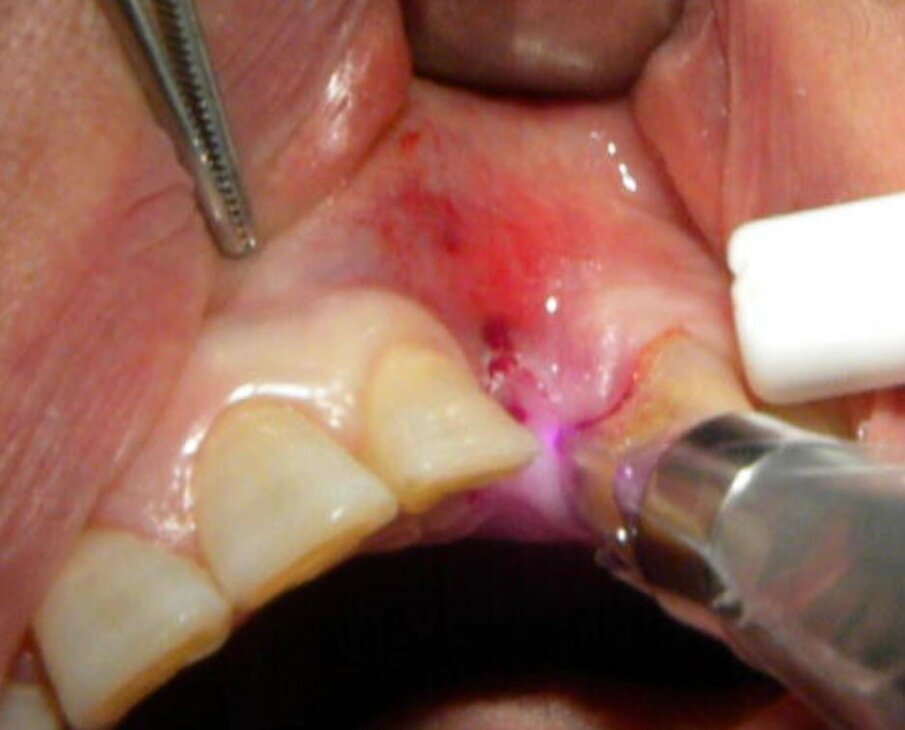

Fig. 10 - Caso clinico 3. Scopertura implantare: è possibile eseguire una precisa opercolectomia.